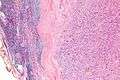

| Micrograph of an intranodal palisaded myofibroblastoma. H&E stain. | |

They have a rim of peripheral lymphoid tissue (remnant of a lymph node) and consist of spindle cells with nuclear palisading. Red blood cell extravasation is common and blood vessels surrounded by collagen with (fine) peripheral spokes (amianthoid fibers) are usually seen.[2]

Immunostains for smooth muscle actin and cyclin D1 are characteristically positive. The main histologic differential diagnosis is schwannoma.